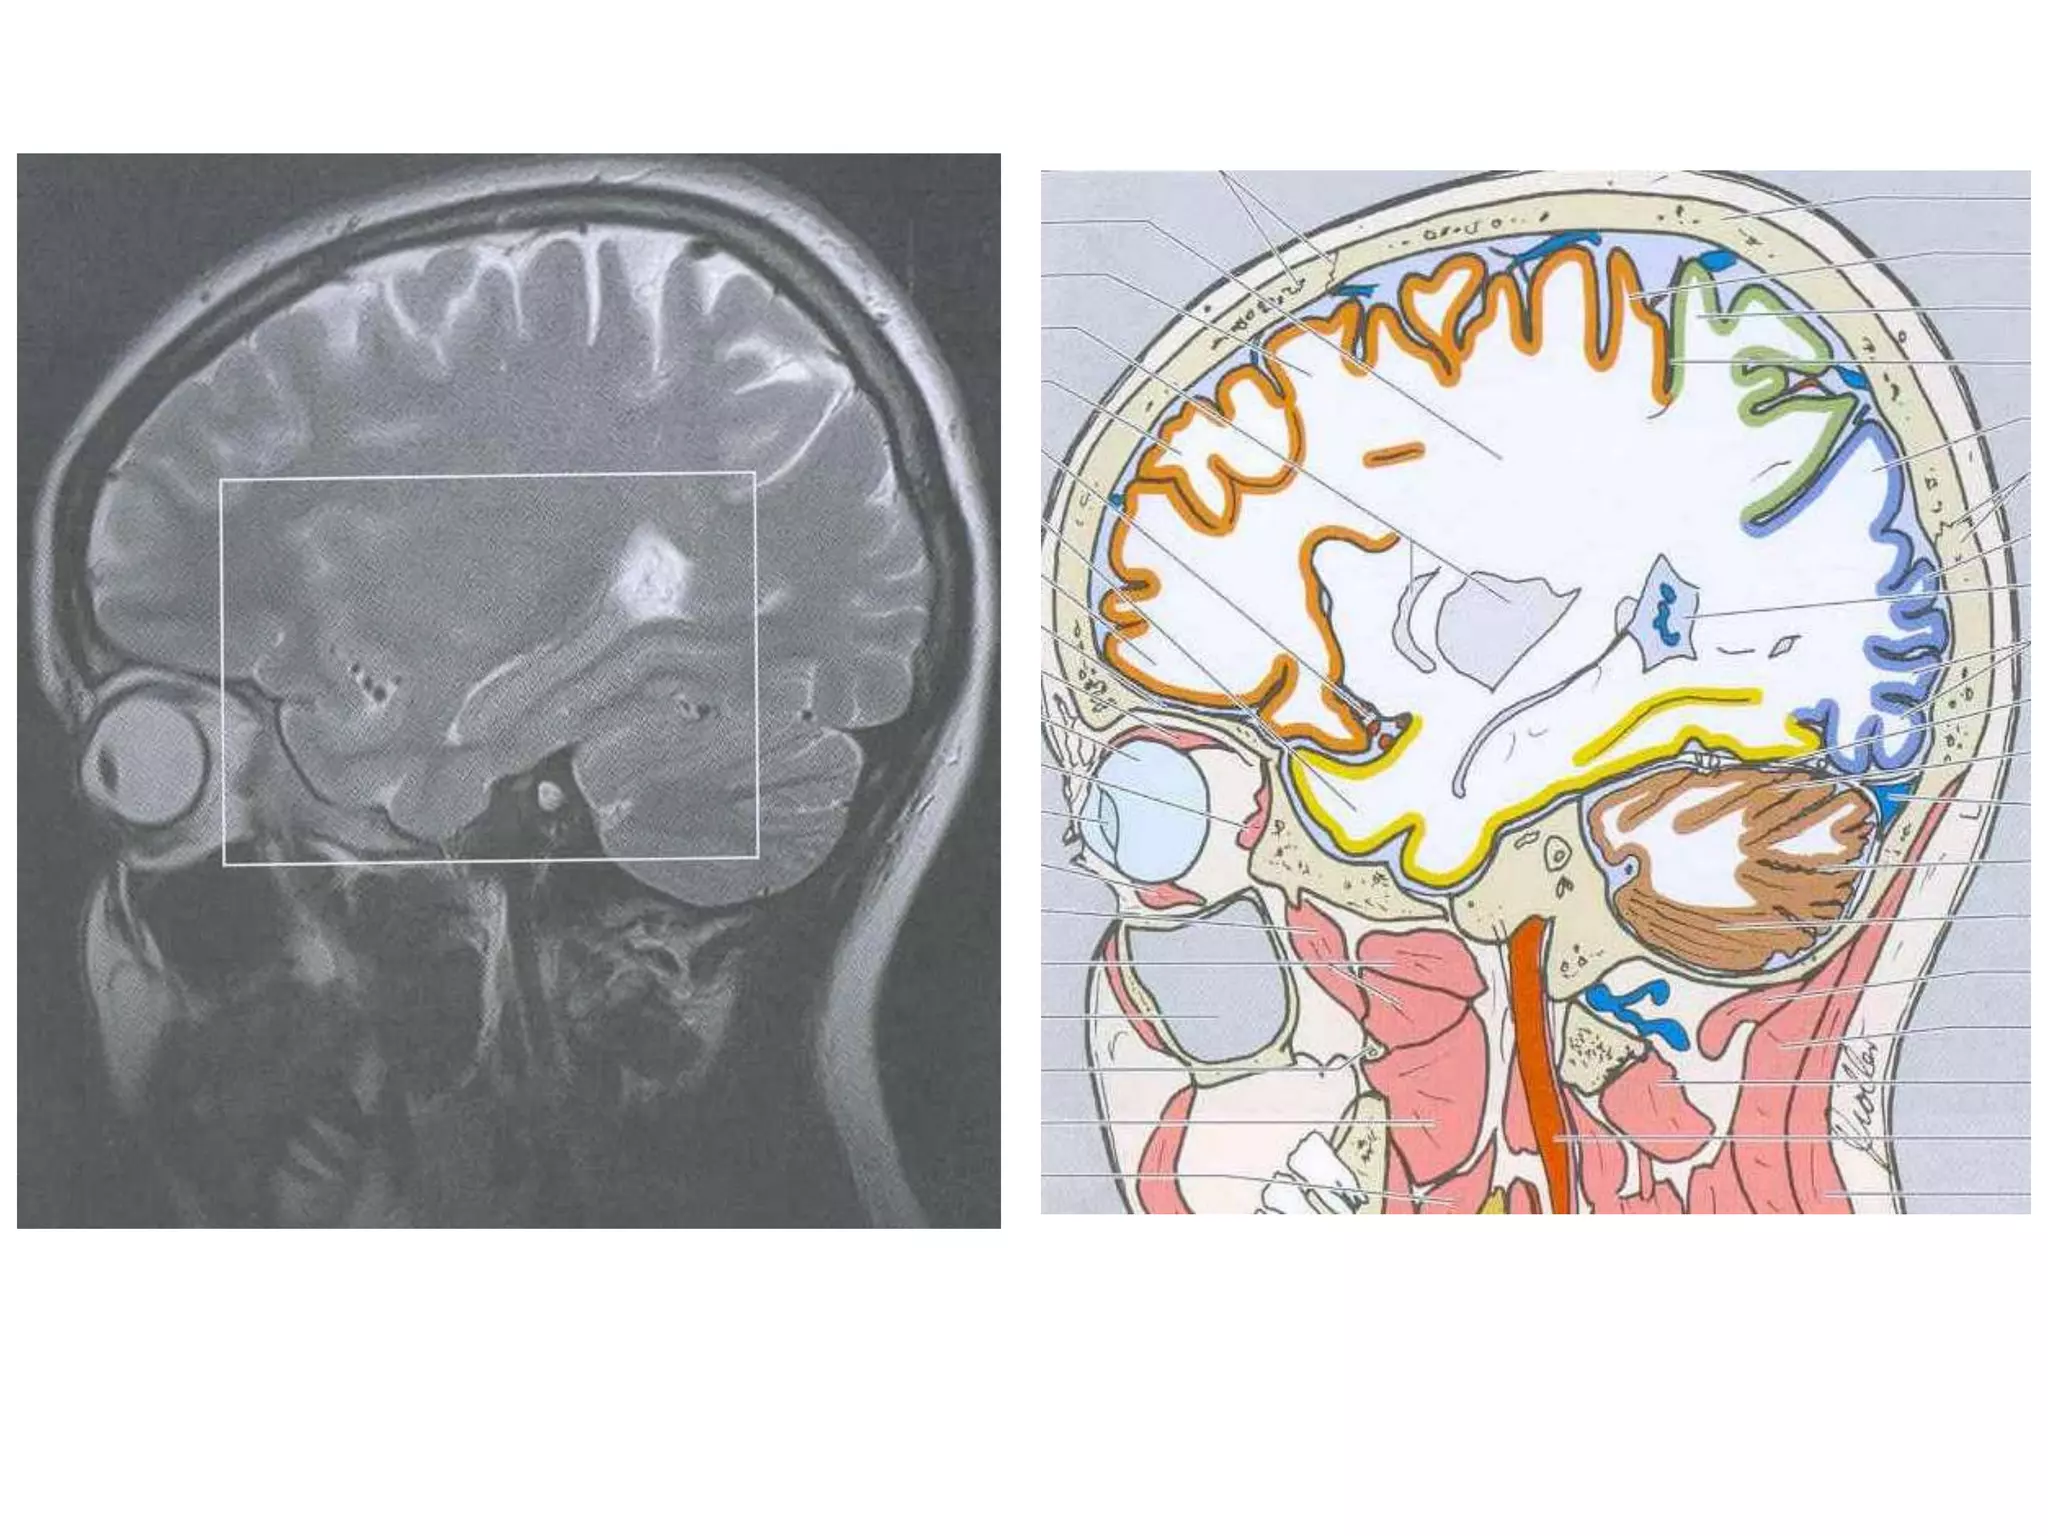

• Anatomy of cerebral hemispheres and mid brain – T1 W

MRI.

• Internal grey - white matter areas – T2 W MRI.

• Saggital and Coronal T1 weighted MRI – accurate

assessment of ventricles and C. callosum

Coronal : frontal horns – inverted triangle

body – flattened

temporal horns – like ‘C’ on its sides.